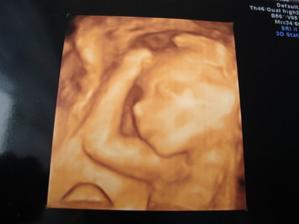

Ale 10.11 jsem se obědnala na nahrávku 3D záznamu tak jse s manželem už moc těšíme jak budeme drobinka pozorovat snad bude snáma spolupracovat uvidíme 🙂)

.........10.11.09 3D UTZ byl zážitek a manžel jsi to užíval protože vý že to bylo asi už naposled co viděl našeho drobinka ještě v bříšku tedka jsi už bude muset počkat do porodu.